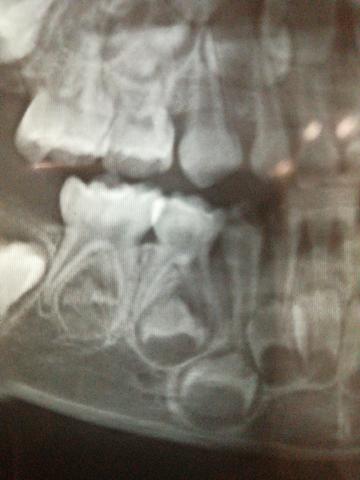

右下第四颗乳牙(84)

从片子情况看,这个乳牙是完全可以保留的。可能需要做根管治疗。